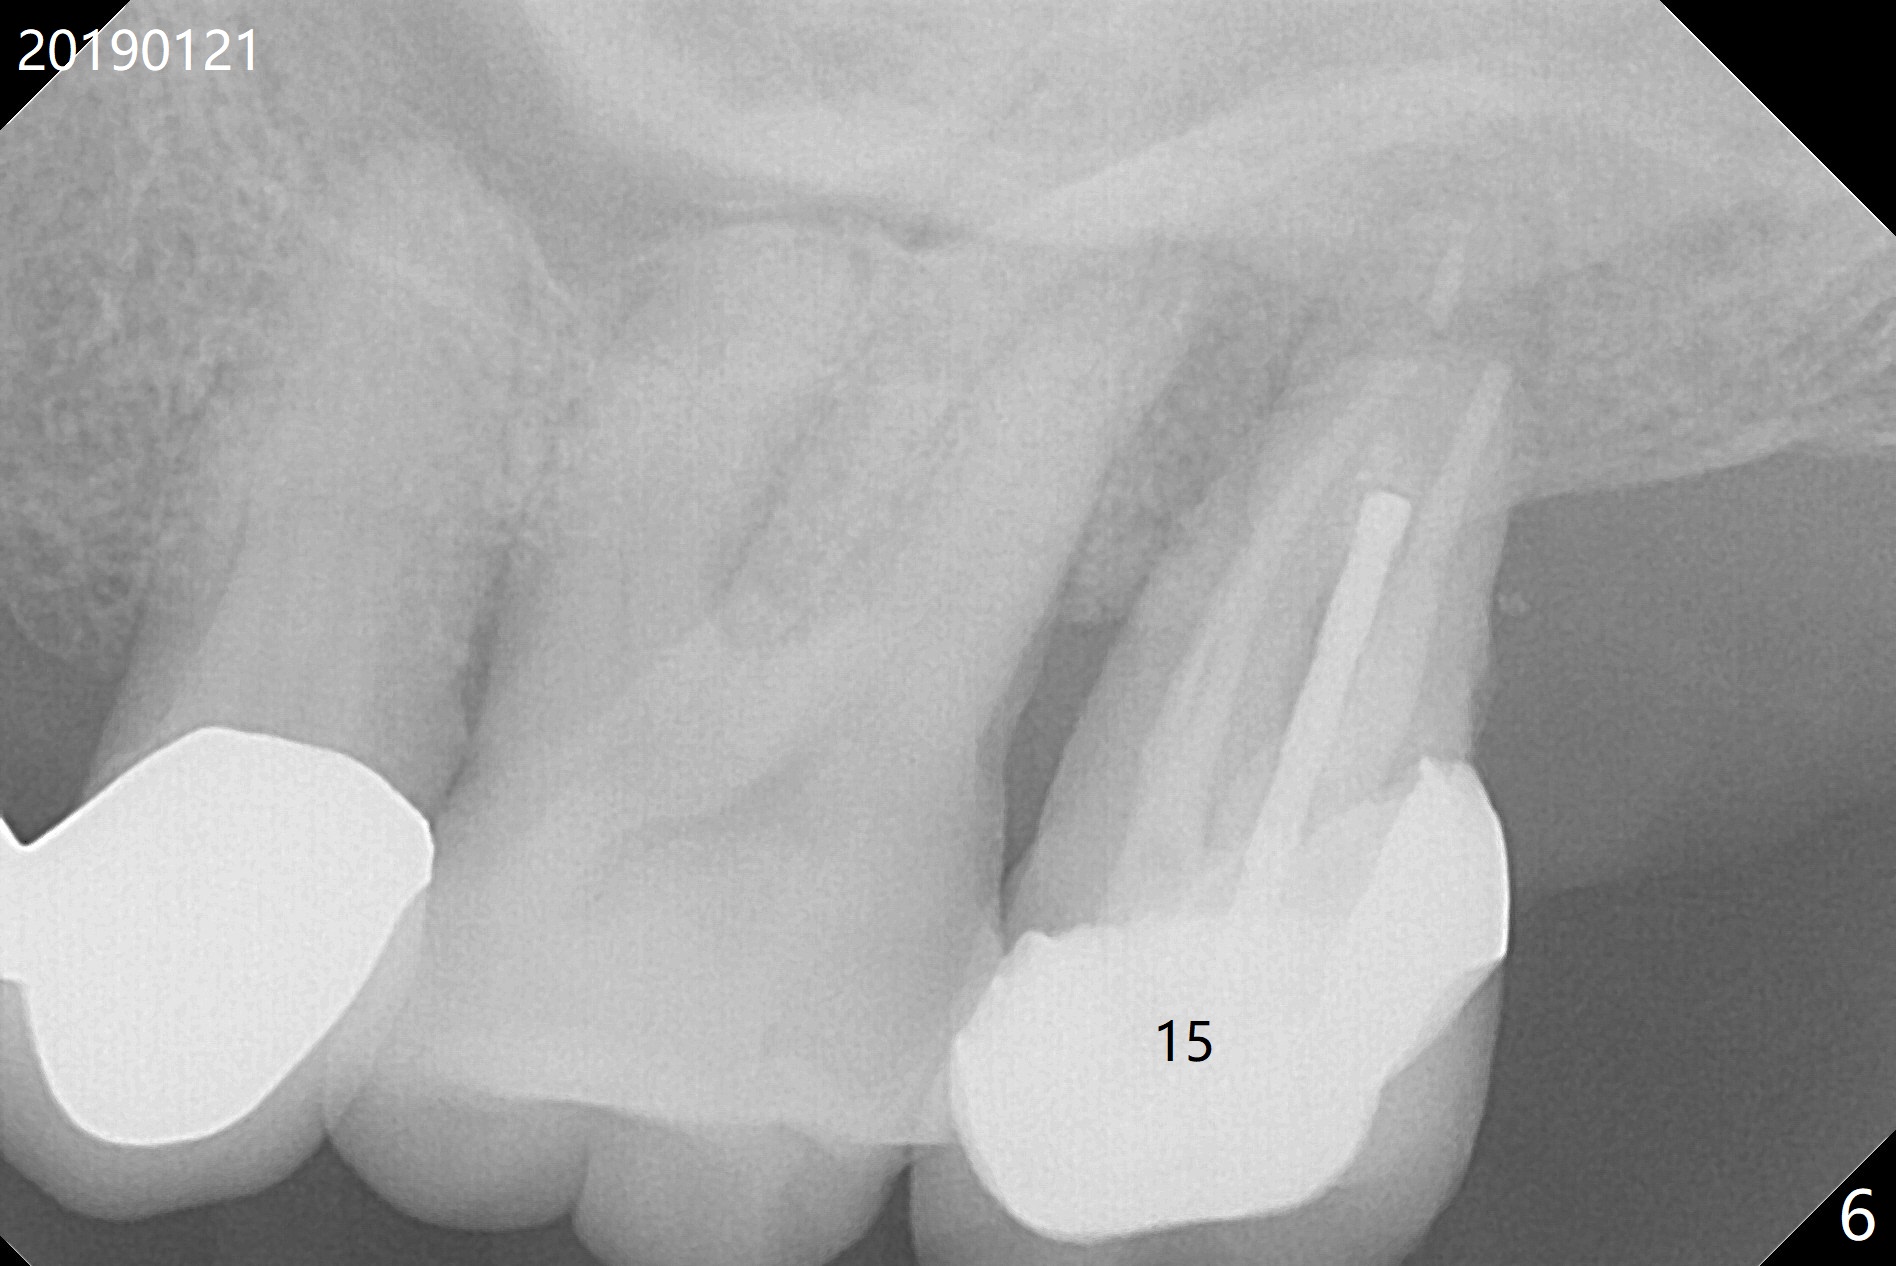

A 71-year-old man finally agrees to have an implant to be placed at #2 four years being our patient. The break point is that the crown at #30 needs recementation. The tooth #2 was missing when he presented for new patient exam (Fig.1,2). The bone loss between #30 and 31 is mild (Fig.1 *) with a small diastema (Fig.2 >). Porcelain chips at the pontic (Fig.3 >). The bone height at #2 is limited (Fig.4). The bone loss and the diastema seem to have got worse in the last 3-4 years (Fig.5). The tooth #15 has mobility with exposure of the buccal roots (Fig.6). Because of bruxism, consider flap surgery to bury the implant at #2 with guide.